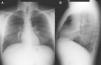

Caso clínicoPaciente varón de 40 años, diagnosticado de enfermedad de N-P con afectación hepática y pulmonar. Antecedentes personales: hepatoesplenomegalia diagnosticada desde los 6-7 meses de vida. Ingresa a los 6 años de edad por cuadro de astenia, anorexia, decaimiento y fiebre. Se le realizó radiografía de tórax posteroanterior y lateral (PA-L), en la que se apreció un patrón reticular difuso. Ante los hallazgos radiográficos y la presencia de hepatoesplenomegalia se sospechó enfermedad por depósito, realizándose biopsia de la mucosa rectal y biopsia hepática, que fueron sugestivas de enfermedad de N-P (se visualizaron macrófagos cargados de lípidos). La exploración neurológica y las pruebas de función respiratoria fueron normales. Se confirmó el diagnóstico a los 20 años mediante biopsia de piel con cultivo de fibroblastos, comprobándose un marcado déficit de actividad de esfingomielinasa ácida (ASM) característica de enfermedad N-P que, apoyando el diagnóstico clínico, sería tipo B. A los 38 años se realizó el diagnóstico molecular, en el que se observaron dos mutaciones en el gen SMPD (presentó heterocigosis en mutación p.R608del). Actualmente sigue revisiones en consultas de neumología y en consultas de hepatología, y presenta ictericia intermitente y disnea de máximos esfuerzos (grado 0 MRC). En la exploración física destaca la presencia de mínimos crepitantes bibasales, ictericia subconjuntival y hepatoesplenomegalia. La exploración neurológica es normal. En la analítica los resultados más destacables son: bilirrubina total, 4,17mg/dl; GOT, 38UI/l; GPT, 45UI/l; colesterol total, 221mg/dl. Las pruebas de función respiratoria muestran un patrón ventilatorio normal (FVC,3,84 [87,7%]; FEV1, 3,13 [86%]; FEV1/FVC, 81,58%; TLC, 5,26 [81,8%]) y una alteración leve del intercambio gaseoso (DLCO, 57,5%). Hallazgos radiográficos: radiografía PA-L de tórax (fig. 1 A-B): en el parénquima pulmonar se observa una afectación intersticial reticular difusa de predominio en campos medios e inferiores; TCAR (Aquilion Toshiba de 64 detectores) (fig. 2 A y B): afectación en vidrio deslustrado difusa aunque de predominio en los lóbulos inferiores con engrosamientos septales subpleurales en la pleura periférica, mediastínica y cisuras. No se observan adenopatías mediastínicas ni hiliares. El paciente actualmente no sigue ningún tratamiento y únicamente presenta afectación hepática y pulmonar sin que haya afectación del sistema nervioso central.

El tipo B no parece tener predilección por el sexo y se manifiesta a cualquier edad, aunque es más frecuente antes de los 20 años7. Existe una afectación crónica visceral que se desarrolla de forma lenta2 y presenta una amplia variabilidad en la severidad de los síntomas y los hallazgos clínicos3. La hepatoesplenomegalia es bastante común, con crecimiento esplénico sobre todo1. Se afectan las pruebas de función hepática con aumento de transaminasas y bilirrubina. Puede aparecer trombocitopenia, que podría ser secundaria a infiltración de la médula ósea por células de N-P8, y también puede producir leucopenia. La enfermedad pulmonar es frecuente, y en la mayoría de pacientes aparecen alteraciones en la radiografía o la TACAR de tórax1. La incidencia exacta de la afectación pulmonar es difícil de determinar, pero es raro en adultos y más común en las formas infantiles9. Las células de N-P se acumulan en los septos alveolares, en las paredes bronquiales y en pleura y ocasionan un patrón restrictivo que empeora progresivamente, pudiendo llegar a fallo respiratorio1 con dependencia de oxígeno y/o reducción de la tolerancia al ejercicio físico10. Las pruebas de función respiratoria muestran dicho patrón restrictivo con incapacidad para el intercambio gaseoso, y la ergometría cíclica es anormal en la mitad de los pacientes3. Los hallazgos radiológicos vienen determinados por la existencia de un patrón reticulonodular con engrosamiento de septos interlobulares, opacidades en vidrio deslustrado y a veces nódulos subcentimétricos que pueden estar calcificados2,8,10. En ocasiones la combinación de estos hallazgos produce la imagen llamada crazy paving en TACAR, si bien estos hallazgos no son específicos. El diagnóstico diferencial de este patrón incluye: edema pulmonar, hemorragia pulmonar, linfangitis, proteinosis alveolar, amiloidosis3 y neumonía intersticial no específica. Sin embargo, la asociación con hepatoesplenomegalia debería sugerir enfermedad por depósito2. Existe una pobre correlación entre los test de función pulmonar y los hallazgos morfológicos en la TACAR, lo que implica que los cambios intersticiales no siempre afectan al intercambio gaseoso en un grado significativo3,10. Por lo tanto, la presencia de enfermedad pulmonar intersticial en la radiografía simple o en la TACAR no es necesariamente un indicador fiable de aparición de síntomas clínicos ni de la alteración de las pruebas funcionales respiratorias. Para el estudio de las alteraciones pulmonares en esta enfermedad deben emplearse tanto la radiografía simple de tórax como la TACAR1. En nuestro caso, la afectación pulmonar se evidenció a los 6 años mediante la detección de patrón reticular en la radiografía simple de tórax, pero el paciente no ha presentado hasta el momento actual clínica respiratoria significativa.